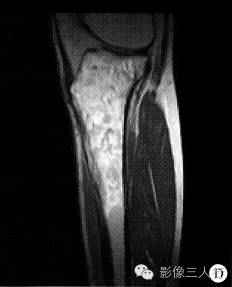

【病例】左胫骨弥漫性非霍奇金淋巴瘤1例X线MR影像表现

3.恶性纤维组织细胞瘤就本例发病的年龄、性别、骨质破坏的形态、范围等均符合恶性纤维组织细胞瘤的特点。但有一重要的不符合之处是破坏区未突破皮质,病变区周围亦无明显软组织肿块。

4.混合性骨肉瘤胫骨近端为好发部位,有成骨,有溶骨,侵及范围跨过骺线,可同时累及皮质及松质骨。但本病未见明确软组织肿块影及肿瘤骨,也未见骨膜反应,故难以支持本病。

PLB较特征的影像表现可概括为:①早期肿瘤仅在骨髓腔内生长,外形保持正常,此时在X线上可表现正常,或仅表现为病变骨质内斑点状的溶骨性低密度,随着肿瘤组织向骨内膜生长,浸润、侵入到骨皮质内,使病变骨呈膨胀性改变,骨皮质呈“筛孔”或“鼠咬”状溶骨性破坏,破坏区边缘不清楚。②肿瘤的MR信号强度与肿瘤内部的组织成分有关。瘤细胞密度高、纤维成分多时,其T1、T2信号强度都相对较低。③骨膜反应较轻微。偶见的骨膜反应为单层型、板层型和针刺状,这种类型的骨膜反应在其他类 型骨原发恶性肿瘤中很少见到。④PLB的增强后MRI常为较均匀的中等或明显强化。⑤PLB的软组织肿块多以病变骨质为中心性,呈包绕性生长。